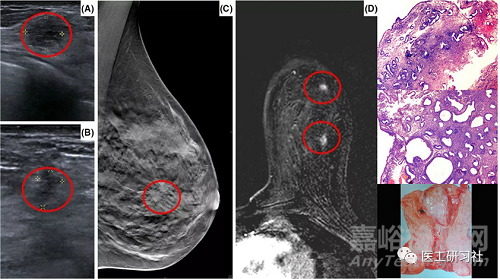

03磁共振

隨著對乳腺癌研究的深入,超聲和乳腺X射線已經(jīng)不能滿足臨床醫(yī)師對腫瘤患者進(jìn)行術(shù)前病理組織學(xué)分級、預(yù)估腫瘤分子分型的要求。磁共振成像(Magnetic Resonance Imaging,MRI)由于對軟組織具有較高的分辨率等特點(diǎn),當(dāng)在乳腺鉬靶X線、CT或超聲檢查中發(fā)現(xiàn)可疑腫瘤組織病灶時(shí),MRI可以提供進(jìn)一步的分析診斷,并且可以避免不必要的活組織檢查。目前常用的磁共振檢查技術(shù)包括:

超聲、乳腺X射線、磁共振、病理對比(來自網(wǎng)絡(luò))